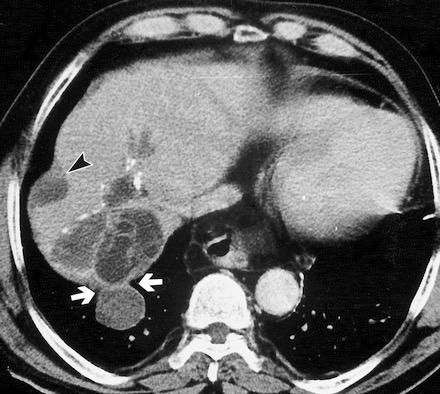

Paciente que ingresa con síntomas de colecistitis aguda. Antecedentes de trauma importante muchos años antes

Zhao L et al. Delayed traumatic diaphragmatic rupture: diagnosis and surgical treatment. © Journal of Thoracic Disease.

J Thorac Dis 2021

Asas

Líquido pericolecistítico

V. biliar con cálculos

Diafragma